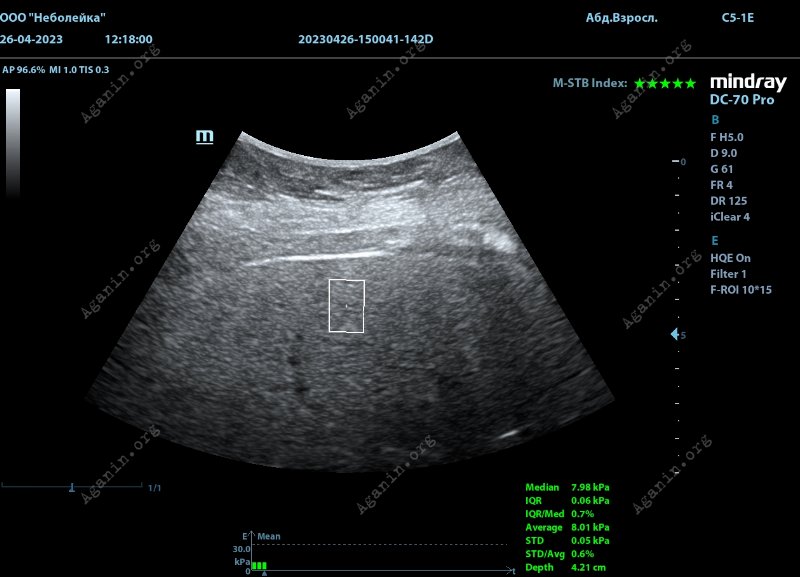

Двухмерная поперечно-волновая эластография (2D-SWE, эластография сдвиговой волной)

Это современный метод измерения степени фиброза, который основан на измерении скорости распространения упругих высокочастотных волн в ткани печени. Для их генерации используется ультразвук. Выполняется с помощью ультразвукового прибора со специальной функцией и особым датчиком.

Во время процедуры пациент ложится на бок, а врач наносит на кожу правого бока специальный гель и помещает на нее ультразвуковой датчик. Датчик излучает короткие импульсы ультразвука, которые проникают в ткань печени формируют механические волны ультразвуковой частоты. Колеблющаяся под действием ультразвука ткань печени распространяет вокруг себя поперечные относительно оси датчика волны деформации ткани печени (это похоже на волны от брошенного в воду камня). Затем прибор измеряет скорость распространения поперчных волн. Чем выше выше скорость поперечных волн, тем выше жесткость ткани печени, и, в свою очередь, выше степень фиброза. Результаты измерений выражаются в единицах кПа (килопаскали). Чем выше значение кПа, тем более жесткой считается печень.